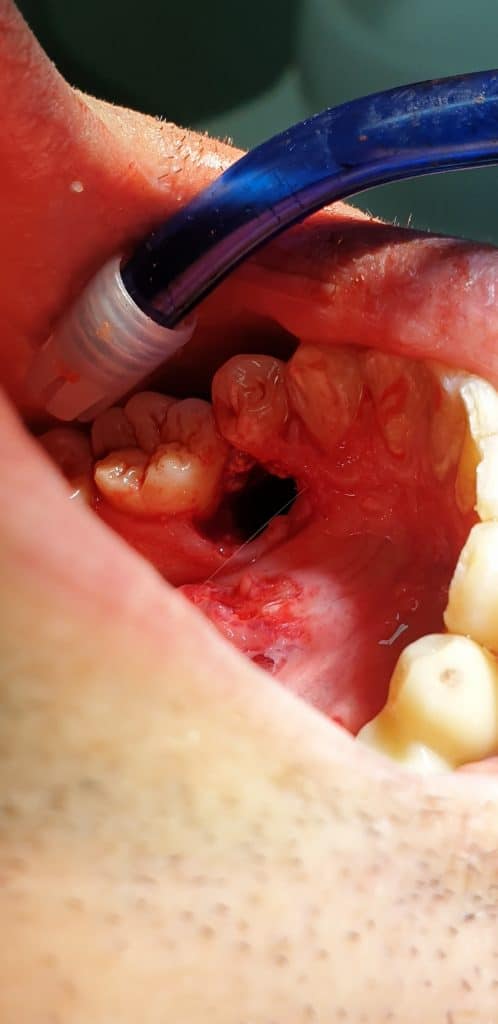

All’esame clinico si evince la posizione anomala del 3.5 e dopo aver effettuato OPT, si opta per l’avulsione dell’elemento dentario interessato.

L’avulsione ha presentato un discreto livello di difficoltà vista la posizione e lo stretto rapporto col 3.4, tanto da ipotizzare l’avulsione anche del 3.4.

L’estrazione è stata portata a termine con successo, il dente ha presentato radice curva e nella zona interessata dell’estrazione si è provveduto a inserire spugnetta emostatica ed osso sintetico e sutura.